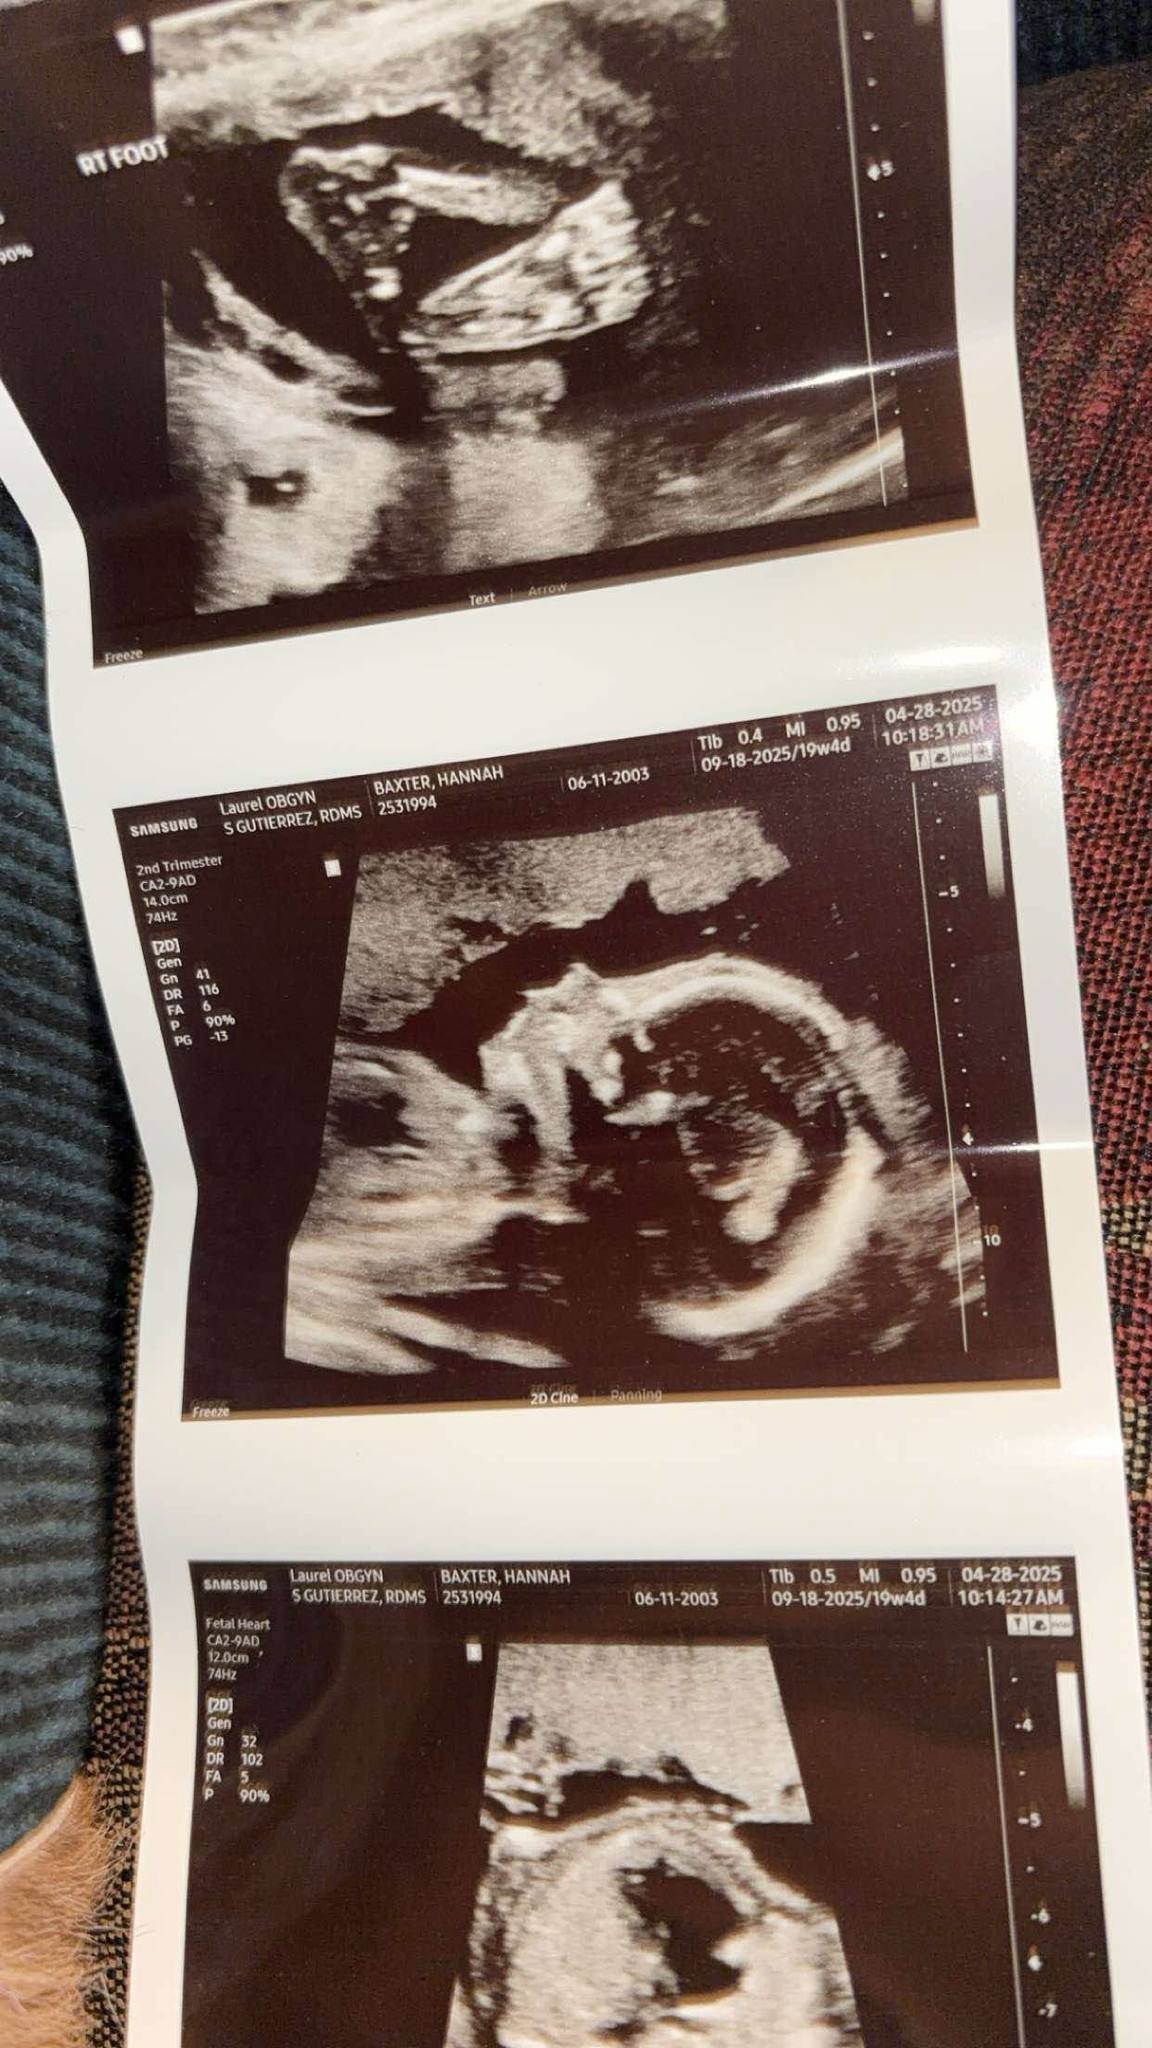

This past Monday, I went to the OB for my 20-week ultrasound with a mix of excitement and anxiety. After experiencing a miscarriage last year, I had no idea what to expect, but I tried to keep a positive mindset, especially since I was about to see my beautiful baby. The ultrasound tech was amazing, explaining everything and reassuring me that things looked great—until she said something I never imagined I’d hear.

She gently asked, “Do you remember what your daughter’s ultrasound looked like?” I replied, “Kinda, not really, haha.” Then, I sensed something was off. She paused and said, “I’m so sorry to tell you this, but your baby has only the right side of her heart. It’s called hypoplastic left heart syndrome.”